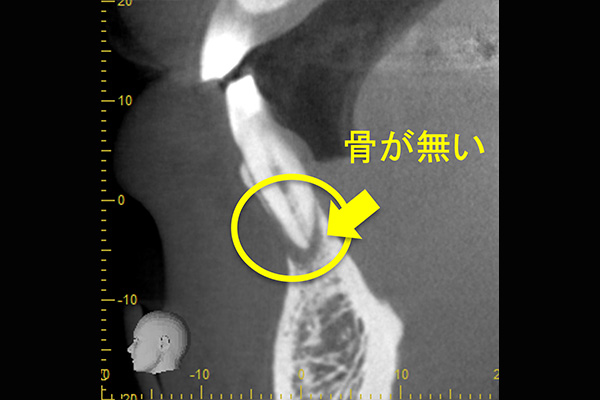

他院にて、抜歯といわれ、セカンドオピニオン目的に来院されました。

①自覚症状なし・歯肉にサイナストラクト(排膿路)あり

②初診時レントゲン解説

・歯根周囲に透過像(黒い影)あり

・遠心根根管充填:アンダー